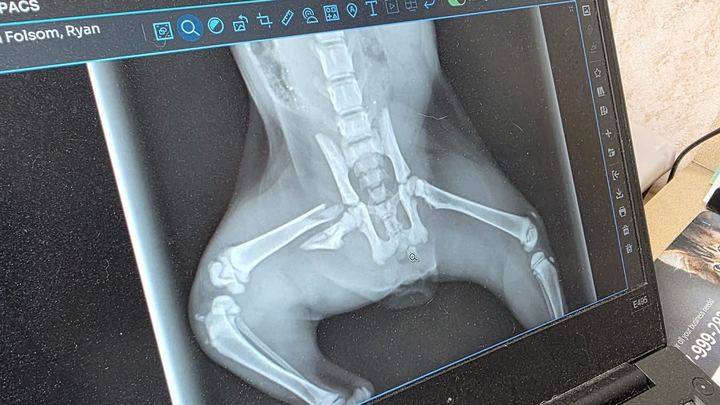

We were driving down 61st and Lewis when Ryan stopped in traffic to save this kitty. She was laying in the middle of the road, unable to move. We rushed her to the vet and found out she has a broken leg that will need to be amputated.

As most of you know, we love to rescue, and we will be taking this kitty home to give her a good life. We’re putting this out here to see if anyone could help contribute to her surgery she will be having Monday. Thank you for reading.